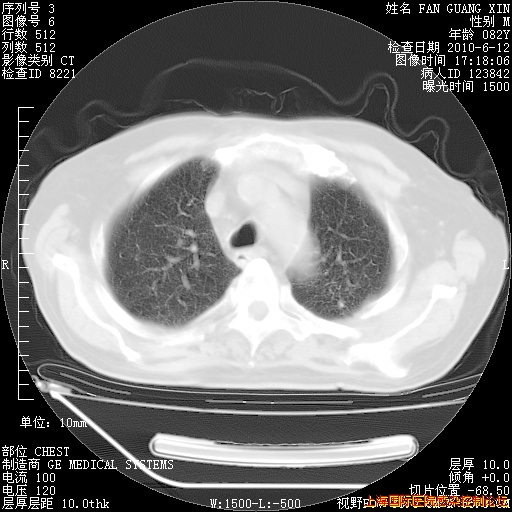

6月12日肺窗

整整相隔30天的肺部CT好像有所好转啊。甲强龙减量第3天,需要观察体温。

海管,自昨日你和我通完话后,不知您岳父消化道症状有无缓解?体温怎样?阅读7.12日胸部ct,个人认为目前激素治疗是有效的,甲强龙减量是适宜的。因在抗痨治疗,需密切观察肝功、肾功能和血常规。不过,老年、长期住院和大量使用激素,很担心菌群失调发生